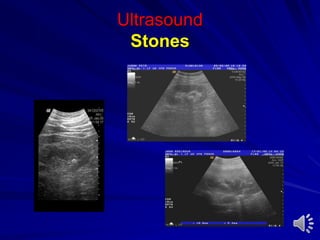

Ultrasound

Stones

Dilatation of collecting system